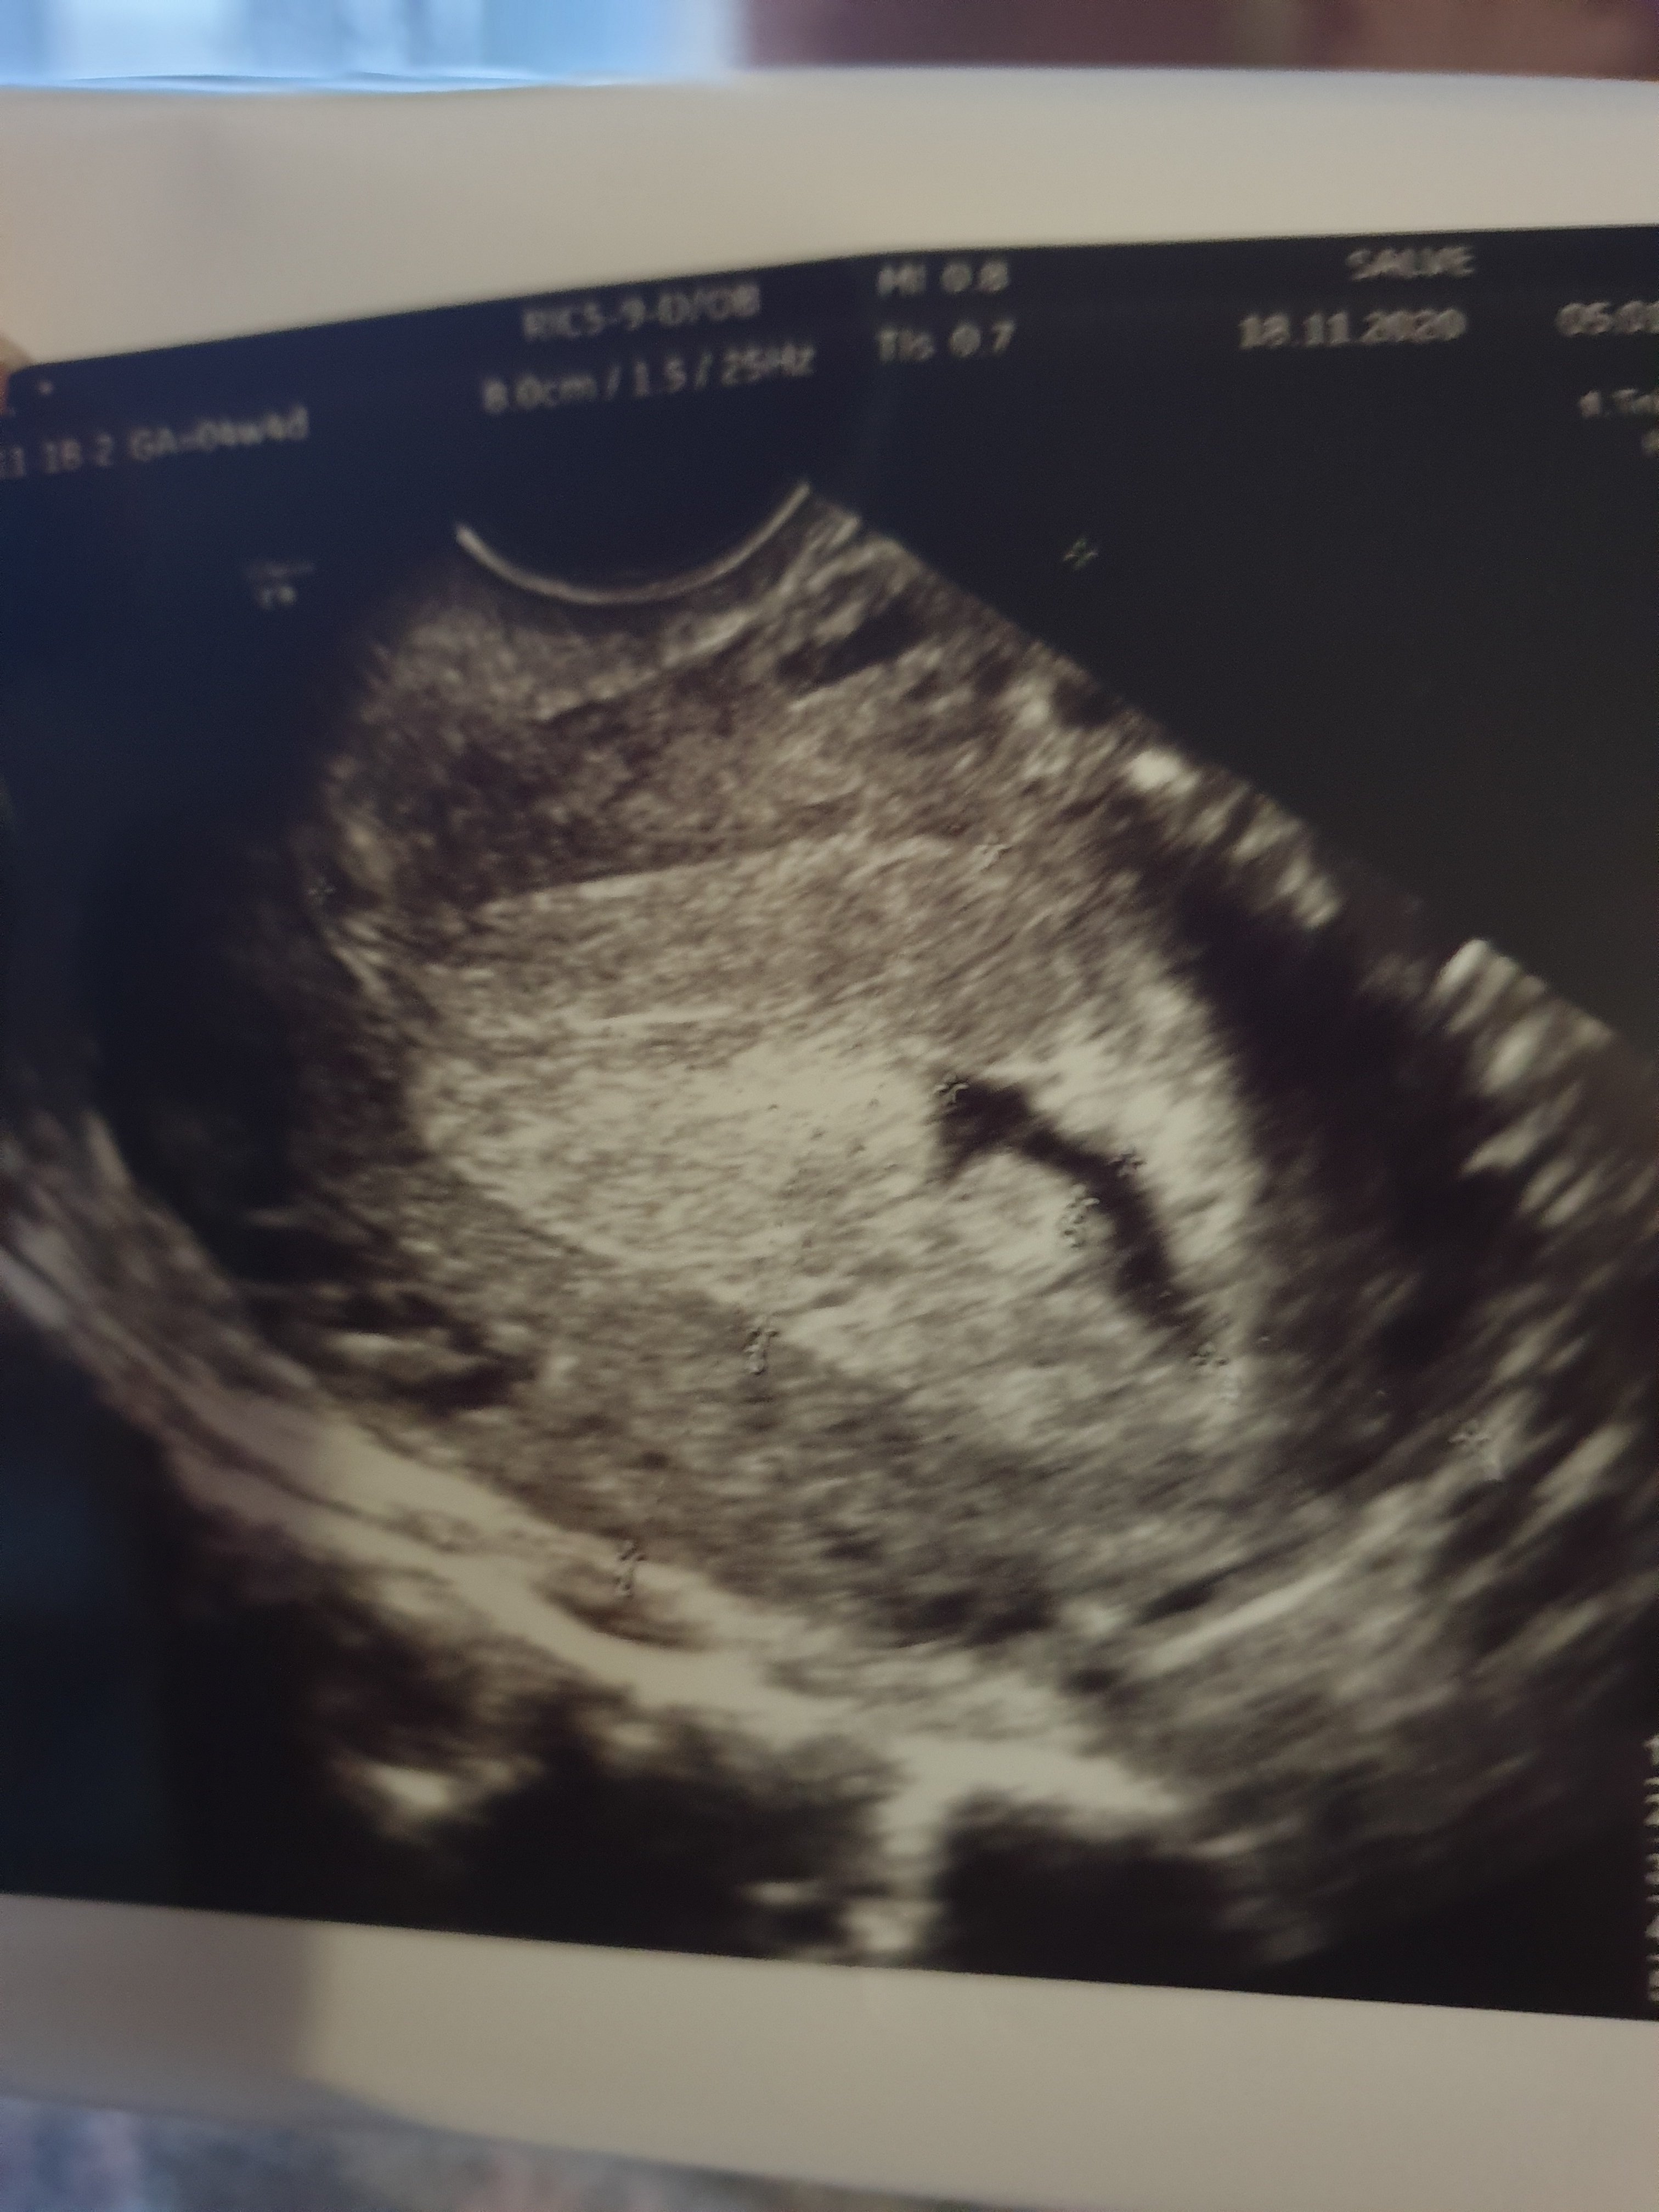

Witam , po 3 dniach spozniajacego się okresu udałam się na usG. Pani doktor wyliczyla że jestem w 4 tc. natomiast w trakcie wykonywania usg powiedziala że pecherzyk ciazowy jest nieprawidłowy i jej zdaniem macica szykuje się do poronienia.w celu potwierdzenia napisala skierowanie na badanie bthcg.Wynik wzrósł po 48 h z 648 na 1630 . Czy w takiej sytuacji mam jakieś szanse na rozwój tej ciąży ? Czy któraś z Mam miała taką sytuację? Dołączam zdjęcie z usg

Tylko tutaj ewidentnie pęcherzyk nie jest pusty.

Jest płaski, owszem, ale nie takie pęcherzyki się dobrze rozwijały i wszystko było okej. Nie rozumiem na jakiej podstawie lekarka już teraz określiła że macica szykuje się do poronienia z skoro jest pęcherzyk, a beta ładnie urosła.

Faktycznie pęcherzyk nie wygląda dobrze. Jest nieprawidłowy. Natomiast w 4tc to zupełnie normalne, że jest pusty. Beta nie powie tak naprawdę nic, oprócz tego, że ciąża jest. Ani jej prawidłowy przyrost, ani nieprawidłowy i niczym tak do końca nie świadczy. W takim pęcherzyku raczej się zarodek nie rozwinie, choć nie takie cuda natura robiła. Trzeba czekać i mieć nadzieję, że będzie dobrze, ale też przygotować się na najgorsze. ♥

Beta urosla ładnie, ale rzeczywiście ten kształt pęcherzyka nie wróży za dobrze.

@ness. nie wiem gdzie Ty tam coś widzisz w tym pęcherzyku. Dla mnie jest pusty.

Nie umiem na tel zaznaczyć, ale myślałam że to białe coś to właśnie pęcherzyk żółtkowy czy cos takiego.

To białe "coś" nie jest nawet częścią pęcherzyka. Widać, że lekarz nawet tego nie zmierzył.